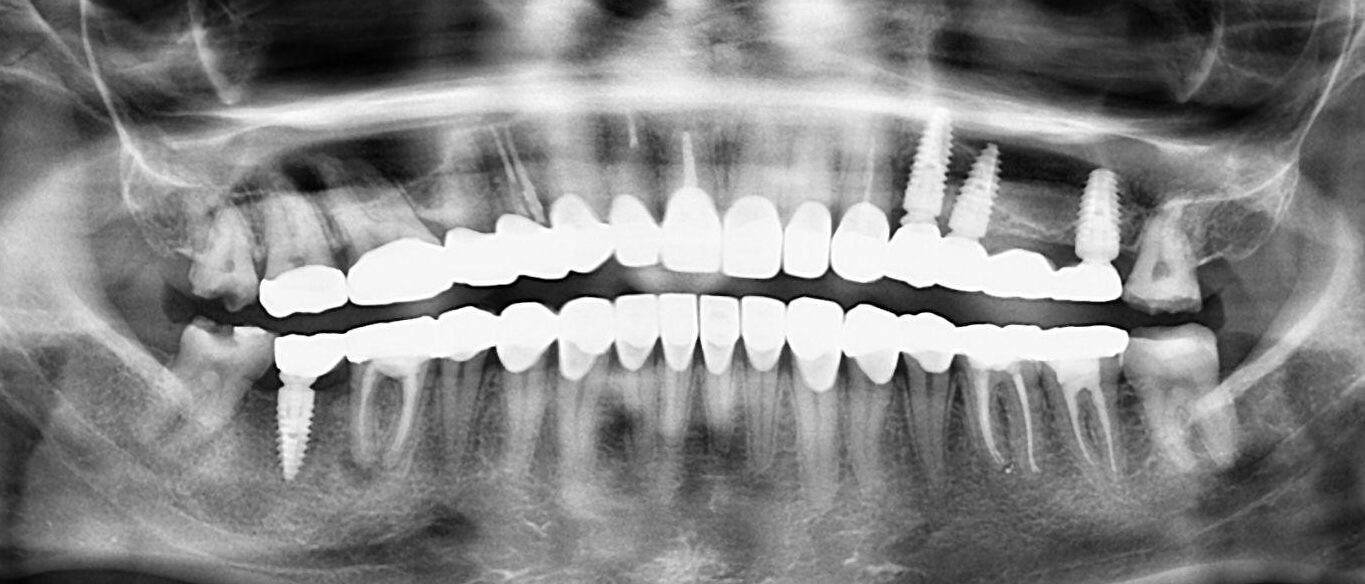

4. What option can be selected for upper jaw of this panoramic X ray?

5. What option cannot be selected for lower jaw of this panoramic X ray?

6. What option cannot be selected for this panoramic X ray?

7. What option cannot be selected for the upper jaw of this panoramic X ray?

8. What option cannot be selected for the lower jaw of this panoramic X ray?